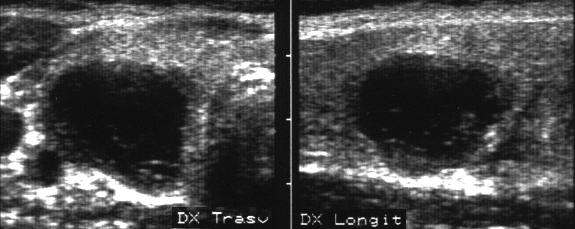

Lob drept , proiectie trasversala si longitudinala.

Femeie 19 ani. Leziune marcant hipoecogen cu intarire posterioara, de 16x20x26mm (4 cc) in lobul drept.

Examen citologic: macrofagi, fara tireocite.